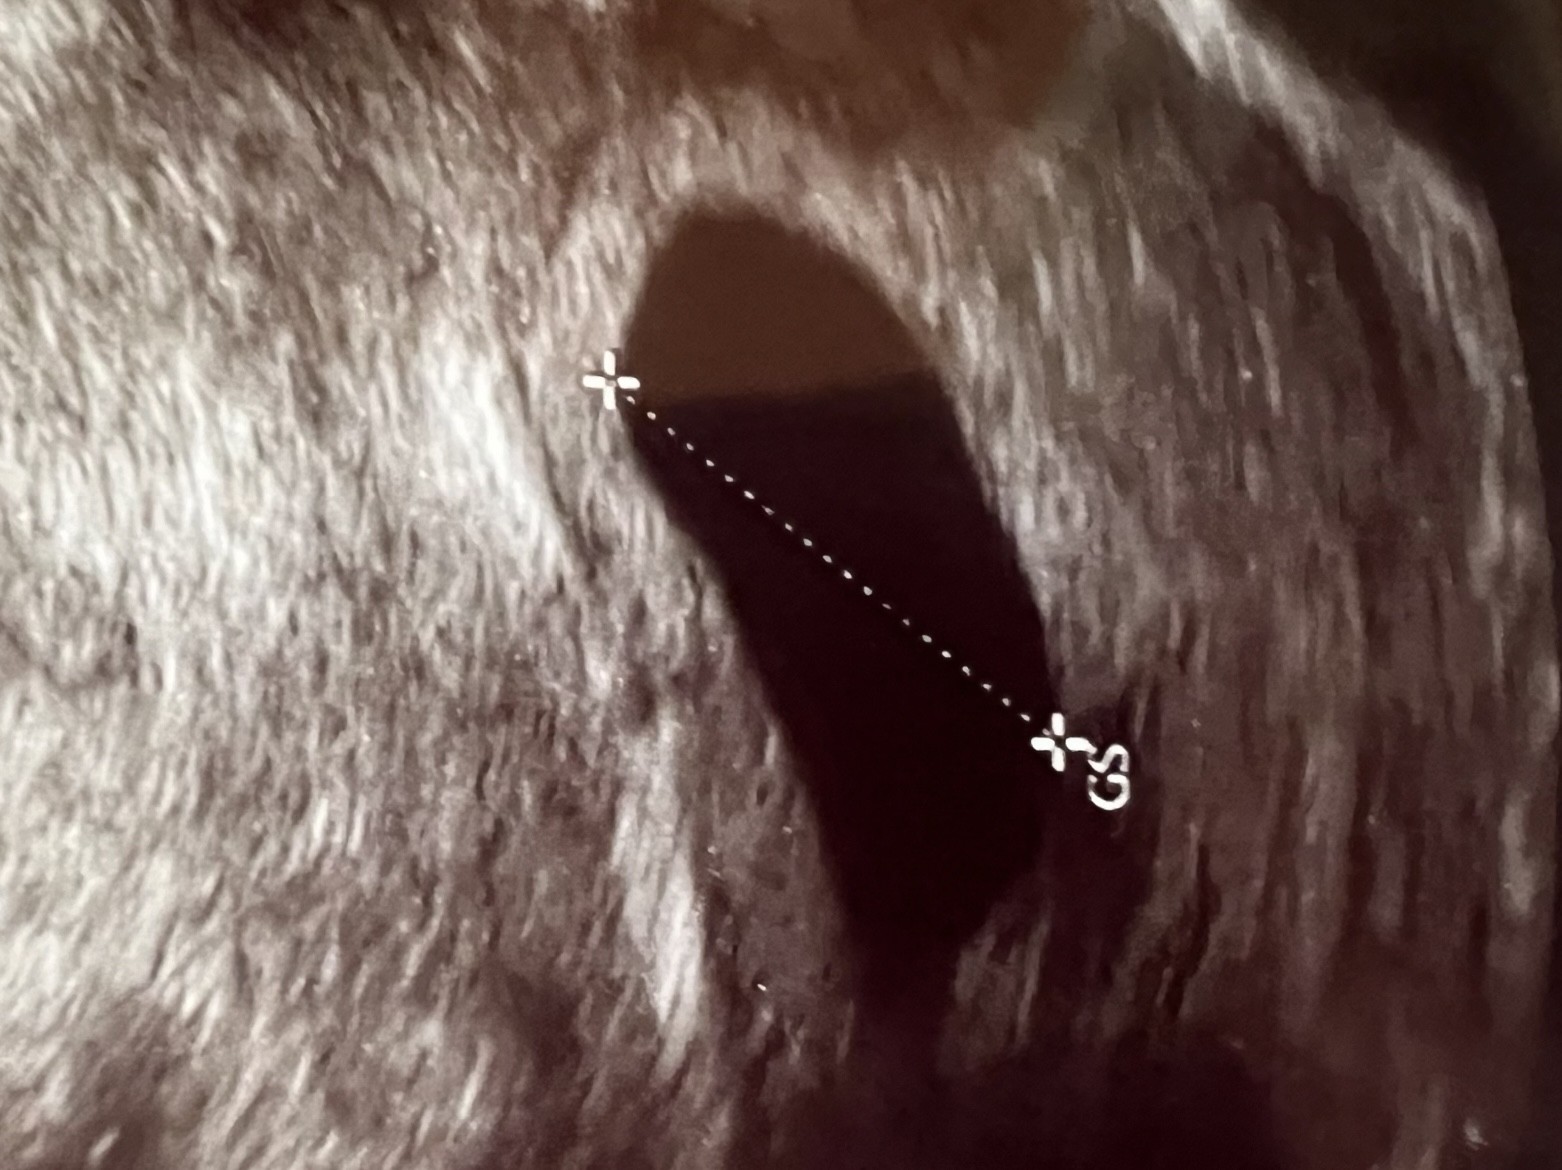

Brak zarodka przy pęcherzyku ciążowym 19 mm

Niestety nie nastawiałabym się pozytywnie. Ciąża oczywiście zawsze może być młodsza, ale tu nie ma i pęcherzyka żółtkowego, ani zarodka :( a beta jest wysoka.

Chyba masz na myśli pęcherzyk żółtkowy a nie ciałko żółte. Pojawienie się pęcherzyka żółtkowego to bardzo dobra oznaka i świadczy o tym, że zaraz uwidoczni się zarodek. Tu niestety nie ma pęcherzyka żółtkowego w pęcherzyku ciążowym. Pozostaje czekać na kolejne USG czy sytuacja się zmieni.